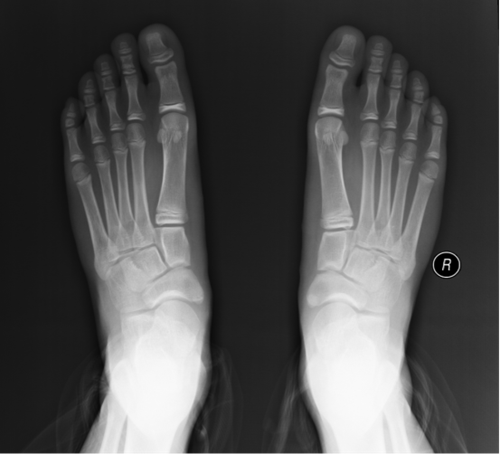

經朋友介紹,帥帥來到青島婦女兒童醫(yī)院小兒骨科門診就醫(yī)。接診專家經過詢問病史、仔細查體,判斷帥帥患有雙足副舟骨。專家進一步完善X線檢查明確診斷,帥帥的確患有雙足副舟骨,這也是引起孩子雙足疼痛的原因。

副舟骨是足部最常見的副骨之一,其起源于足舟骨的繼發(fā)骨化中心,被認為是一種常染色體顯性遺傳導致的畸形,女性多見,常為雙側。

多數(shù)患兒生有副舟骨,卻不自知,因為多數(shù)患兒無明顯癥狀,很多是在偶然的X線檢查時發(fā)現(xiàn),也有很多患兒是因為各種原因的腳疼來門診就診時被發(fā)現(xiàn)的。